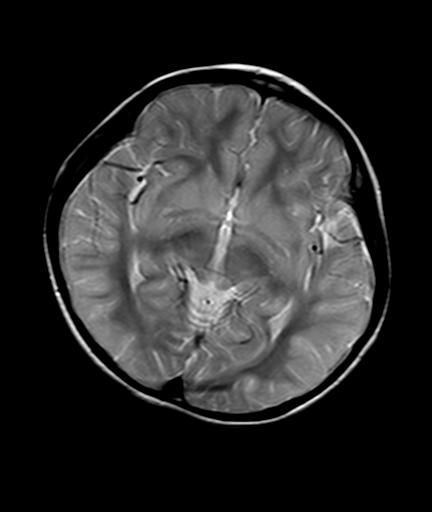

标题: PED2848:脑内病变2

头痛10天、间断呕吐2天。f 6岁

入科化验血清铜及铜兰蛋白均减低,脑脊液正常,血清神经原烯醇化酶明显增高。wbc:5.94x109/l、

临床表现及实验室检查符合肝豆状核变性

符合肝豆状核变性。

mri未见明显异常。但临床支持考虑肝豆状核变性。

肝豆状核变性可能性大。